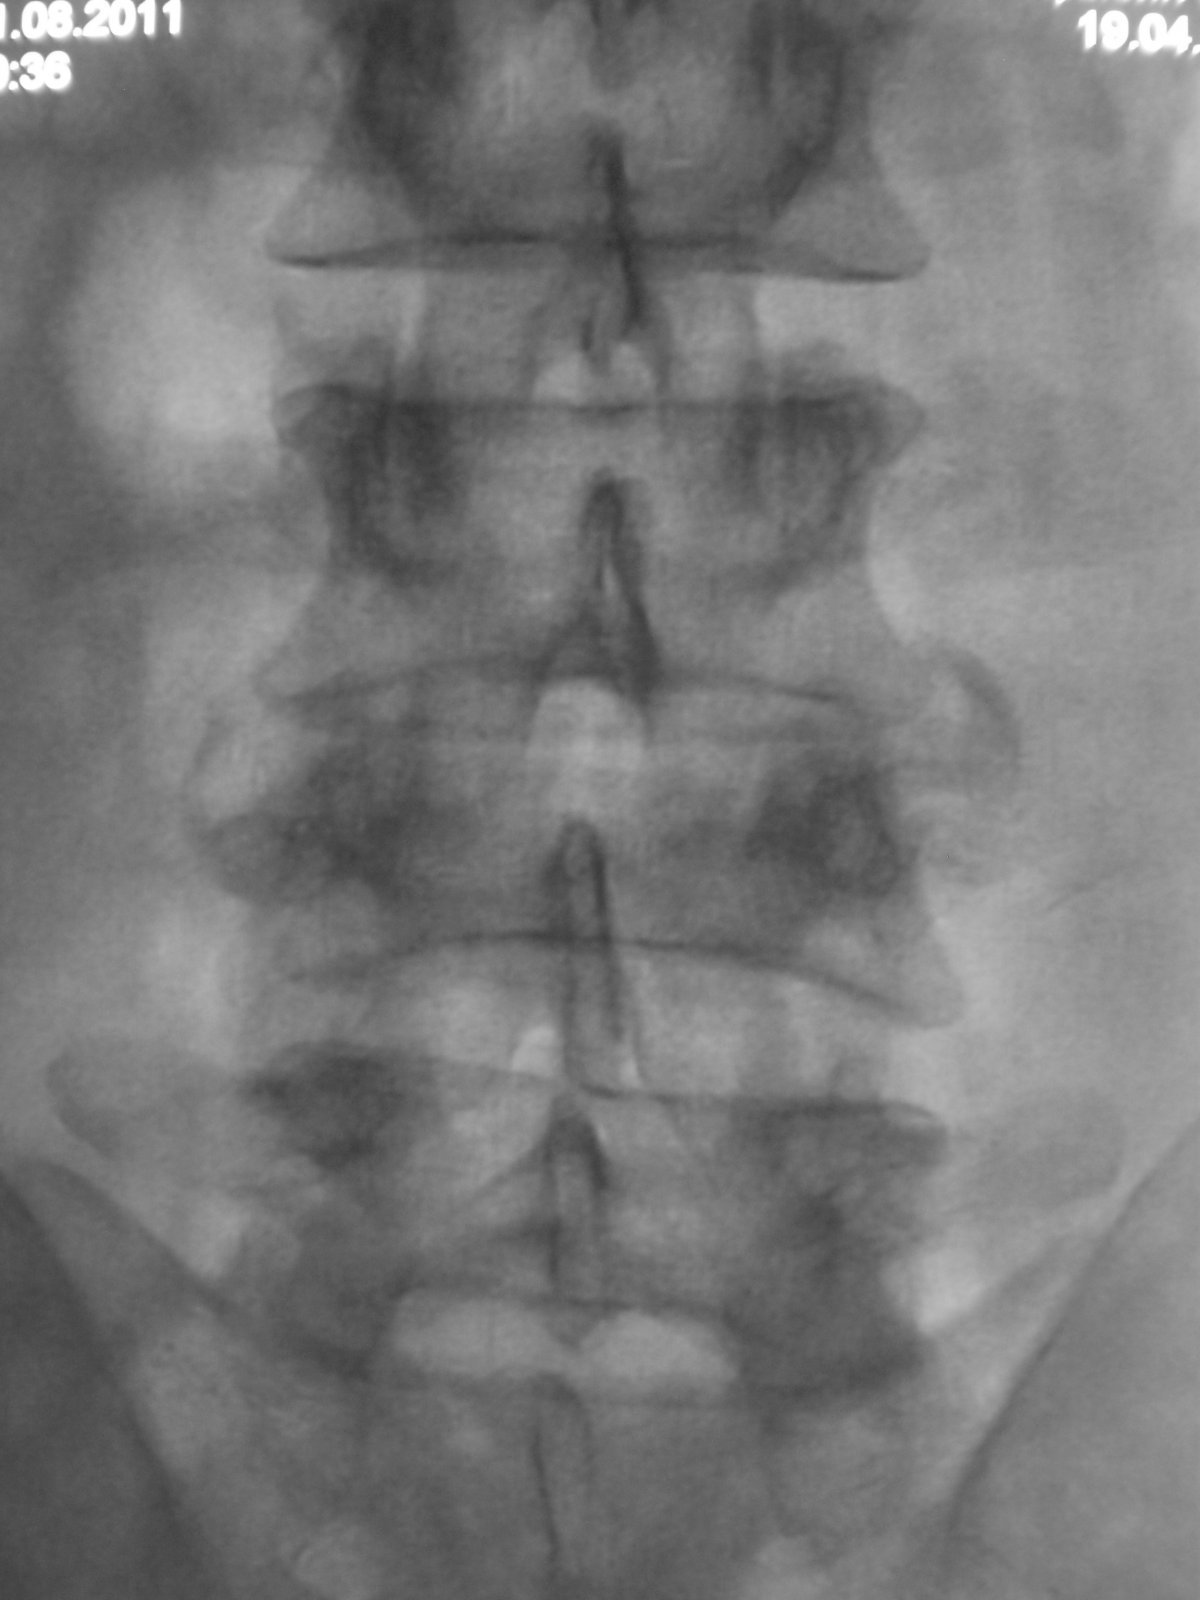

Травма (ДТП) в мае месяце. На контроль пришел на костылях.

Травма (ДТП) в мае месяце. На контроль пришел на костылях

Компрессионный перелом L4. Клин Урбана сдавливает элементы конского хвоста. Синдром конского хвоста(?). Необходима срочная декомпрессия.

пишут не рентгенологи, а клиницисты. О сдавливании элементов хвоста, кроме клиницистов, могут еще судить магниторадиологи. Наш (общий на всех) термин - стеноз позвоночного канала. Еще надо не лениться и указать степень компрессии компрессии тела - легкая (20-25%), умеренная (25-40%), выраженная (больше 40%). А также замерить расстояние между основаниями дуг позвонков в прямой проекции - у L4 оно явно шире, и тогда в дополнение к перелому тела добавится перелом дуги и термин "нестабильный". Для полной красоты следует указывать угол кифотической деформации; критическими значениями являются:  для шейного отдела - 11º,  для грудного – 40º,  для поясничного - 25º

а здесь еще и переломовывих L4. а перелом еще и оскольчатый. с такой картиной можно утверждать что инвалидизация пациенту светит.А в S4 я перелома не вижу.